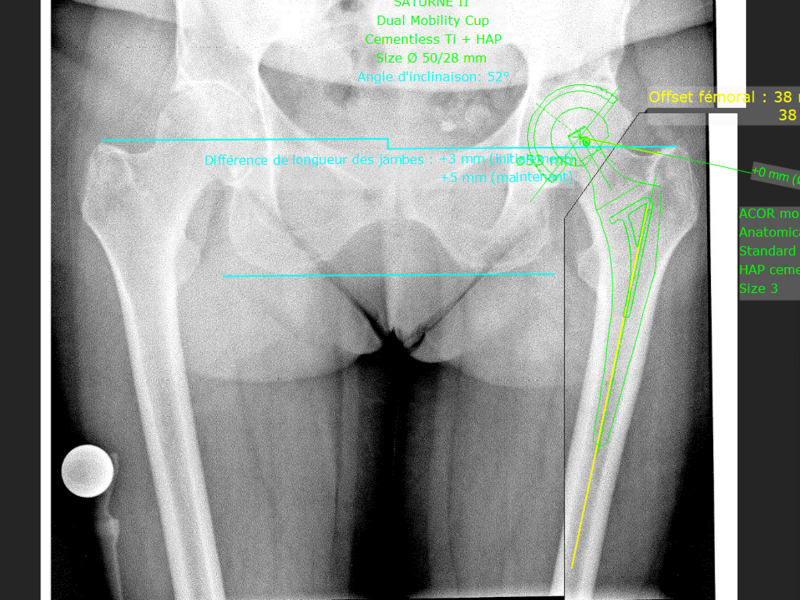

Album photo